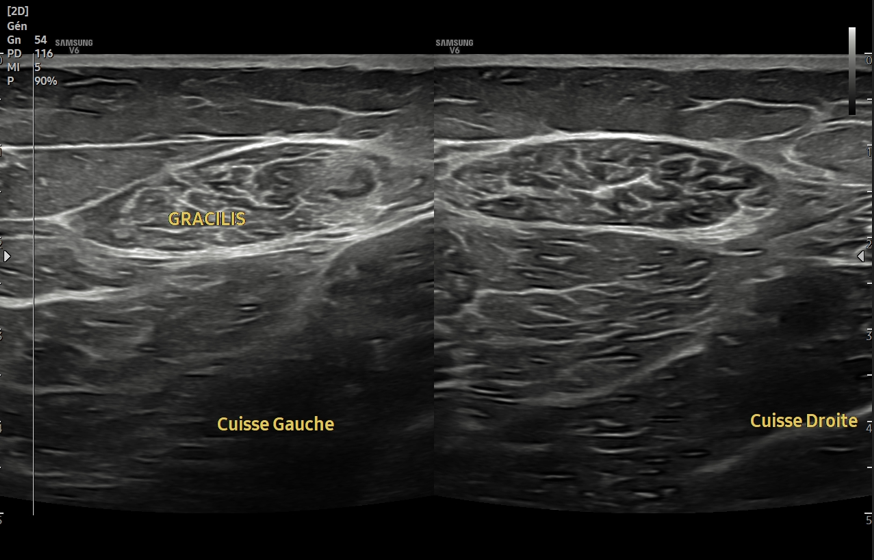

Consent ✅

F 60s

Years of diffuse R gluteal, hip & thigh pain, constant, stairs & sitting aggravates

Seen by orthopaedics to evaluate hip & knee (previous patellectomy this side) - referred to me as unable to identify pain driver & MRI scans 'normal'

MRI pelvis - hip joints & lateral soft tissues are fine

Clear suspect for her pain though, even on first glance - what do you see?

Always check the images yourself - and bear in mind can pick up helpful pathology on non-dedicated series so worth scrutinising it all